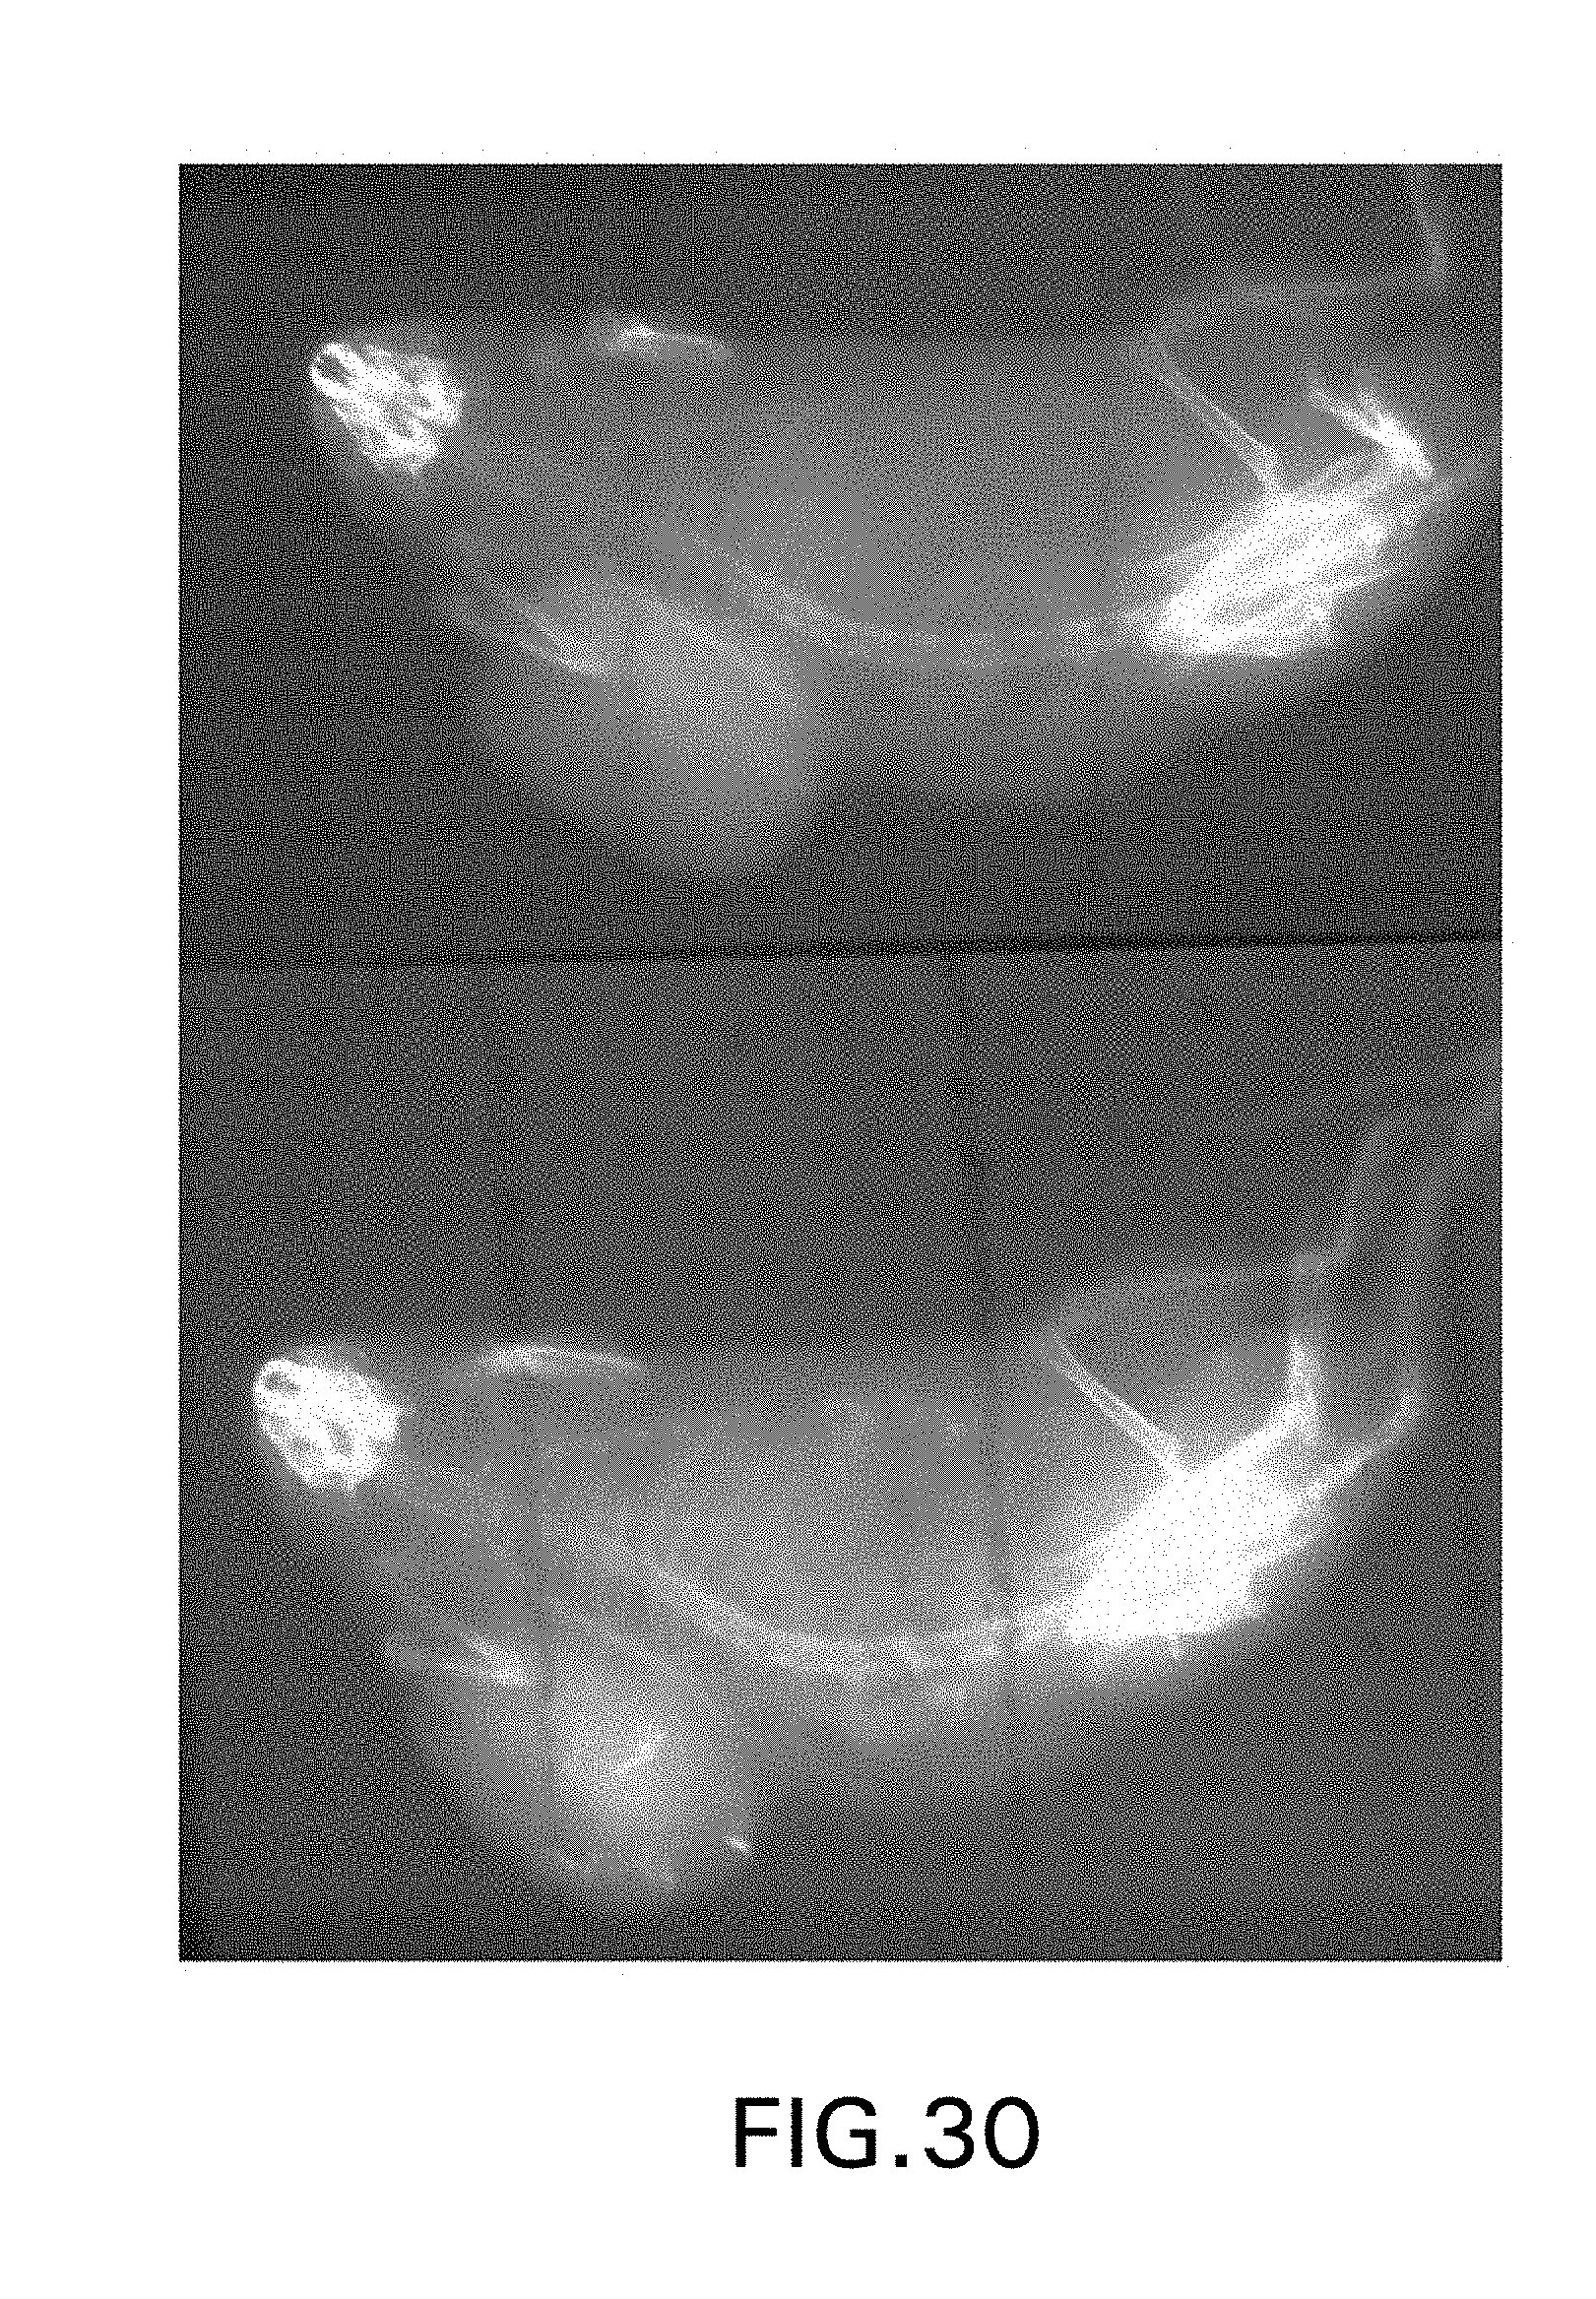

FIG. 30 is a pair of images showing radio-opaque sites of formation of an indigo-like product with an administered indigogenic compound, which are absent prior to administration of the indigogenic compound.